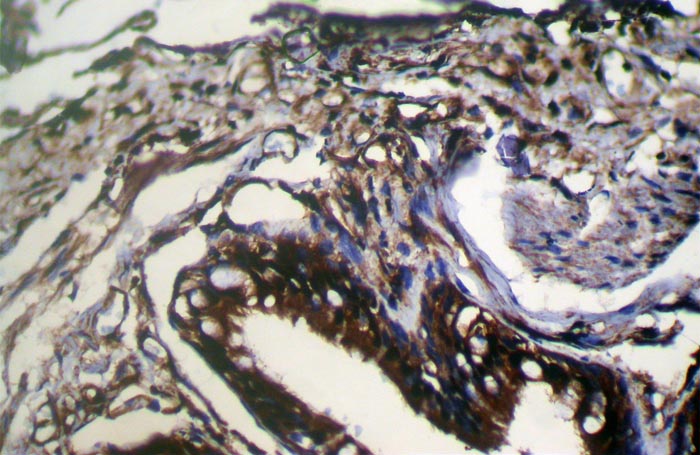

Immunohistochemical analysis of paraffin-embedded Human Lung cancer tissue using #42857 at dilution 1/200.